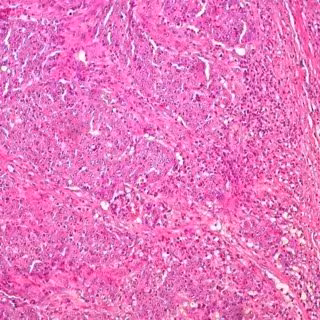

En un enfoque innovador de la prevención y el tratamiento del cáncer colorrectal (CCR), científicos están estudiando maneras de reemplazar los metabolitos que faltan en los pacientes propensos a la inflamación intestinal y el CCR. Un nuevo estudio publicado en 'The American Journal of Pathology' describe cómo la administración de microorganismos intestinales que producen histamina a ratones que carecen de la enzima histidina descarboxilasa (HDC) reduce la inflamación y la formación de tumores.

Se suministró el probiótico antes y después de que los ratones recibieran una dosis única de un carcinógeno del colon (azoximetano) más un producto químico inductor de la inflamación (DSS) para promover la formación del tumor. Quince semanas más tarde, los ratones fueron sacrificados y se extrajeron tejidos para el estudio.

MENOS TUMORES Y MÁS PEQUEÑOS

El probiótico aumentó la expresión de HDC bacteriano y cantidades de histamina en el colon de los ratones. Utilizando la tomografía por emisión de positrones (PET) para visualizar los tumores, se vio evidencia de tumores en los ratones de control y aumento de la captación de glucosa en las paredes del colon. Por el contrario, los roedores a los que se administró el probiótico tuvieron menos tumores y más pequeños y una disminución significativa de las áreas de captación de glucosa.

Las cepas inactivas de 'L. Reuteri' (aquellas deficientes en la actividad de HDC) no proporcionaron efectos protectores. Estos ratones mostraron un mayor número de "puntos calientes" indicativos de la formación de tumores y el incremento de la absorción de glucosa abdominal.

El probiótico activo también redujo la inflamación inducida por el carcinógeno más DSS, como se indica por la expresión de genes de citoquina proinflamatoria suprimida y menos concentraciones de citoquinas en el plasma. El probiótico activo también contrarrestó un aumento en las células inmaduras mieloides inducidas por el carcinógeno.